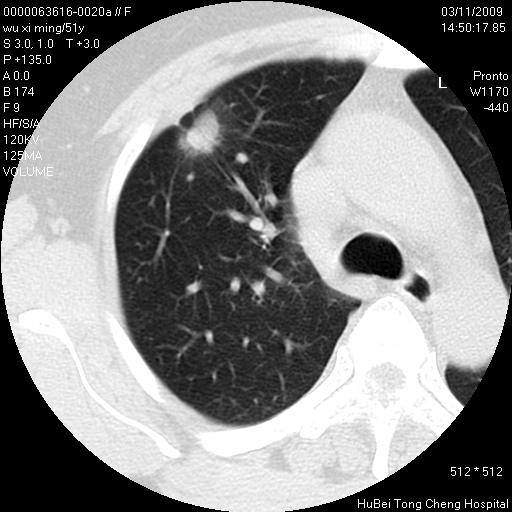

患者 女,51岁。因“胆囊炎,胆囊结石”,行常规术前胸部x线检查发现:右上肺结节病灶,建议行进一步检查。患者无咳嗽、咳痰及咯血等呼吸道症状,近期出现背部疼痛不适。

胸部ct轴位平扫(层厚10mm,螺距1.5,重建间隔10mm;部分层面:层厚3mm,螺距1.0,重建间隔3mm),图像如下:

右肺周围型肺癌伴肺内转移信胸椎转移

1、周围型肺癌。(毛刺正、血管束集征,分叶。)

集束征,胸膜牽拉征,毛刺,淺分葉高度提示ca.

右肺周围型肺癌伴肺内转移及胸椎转移。已无手术机会。